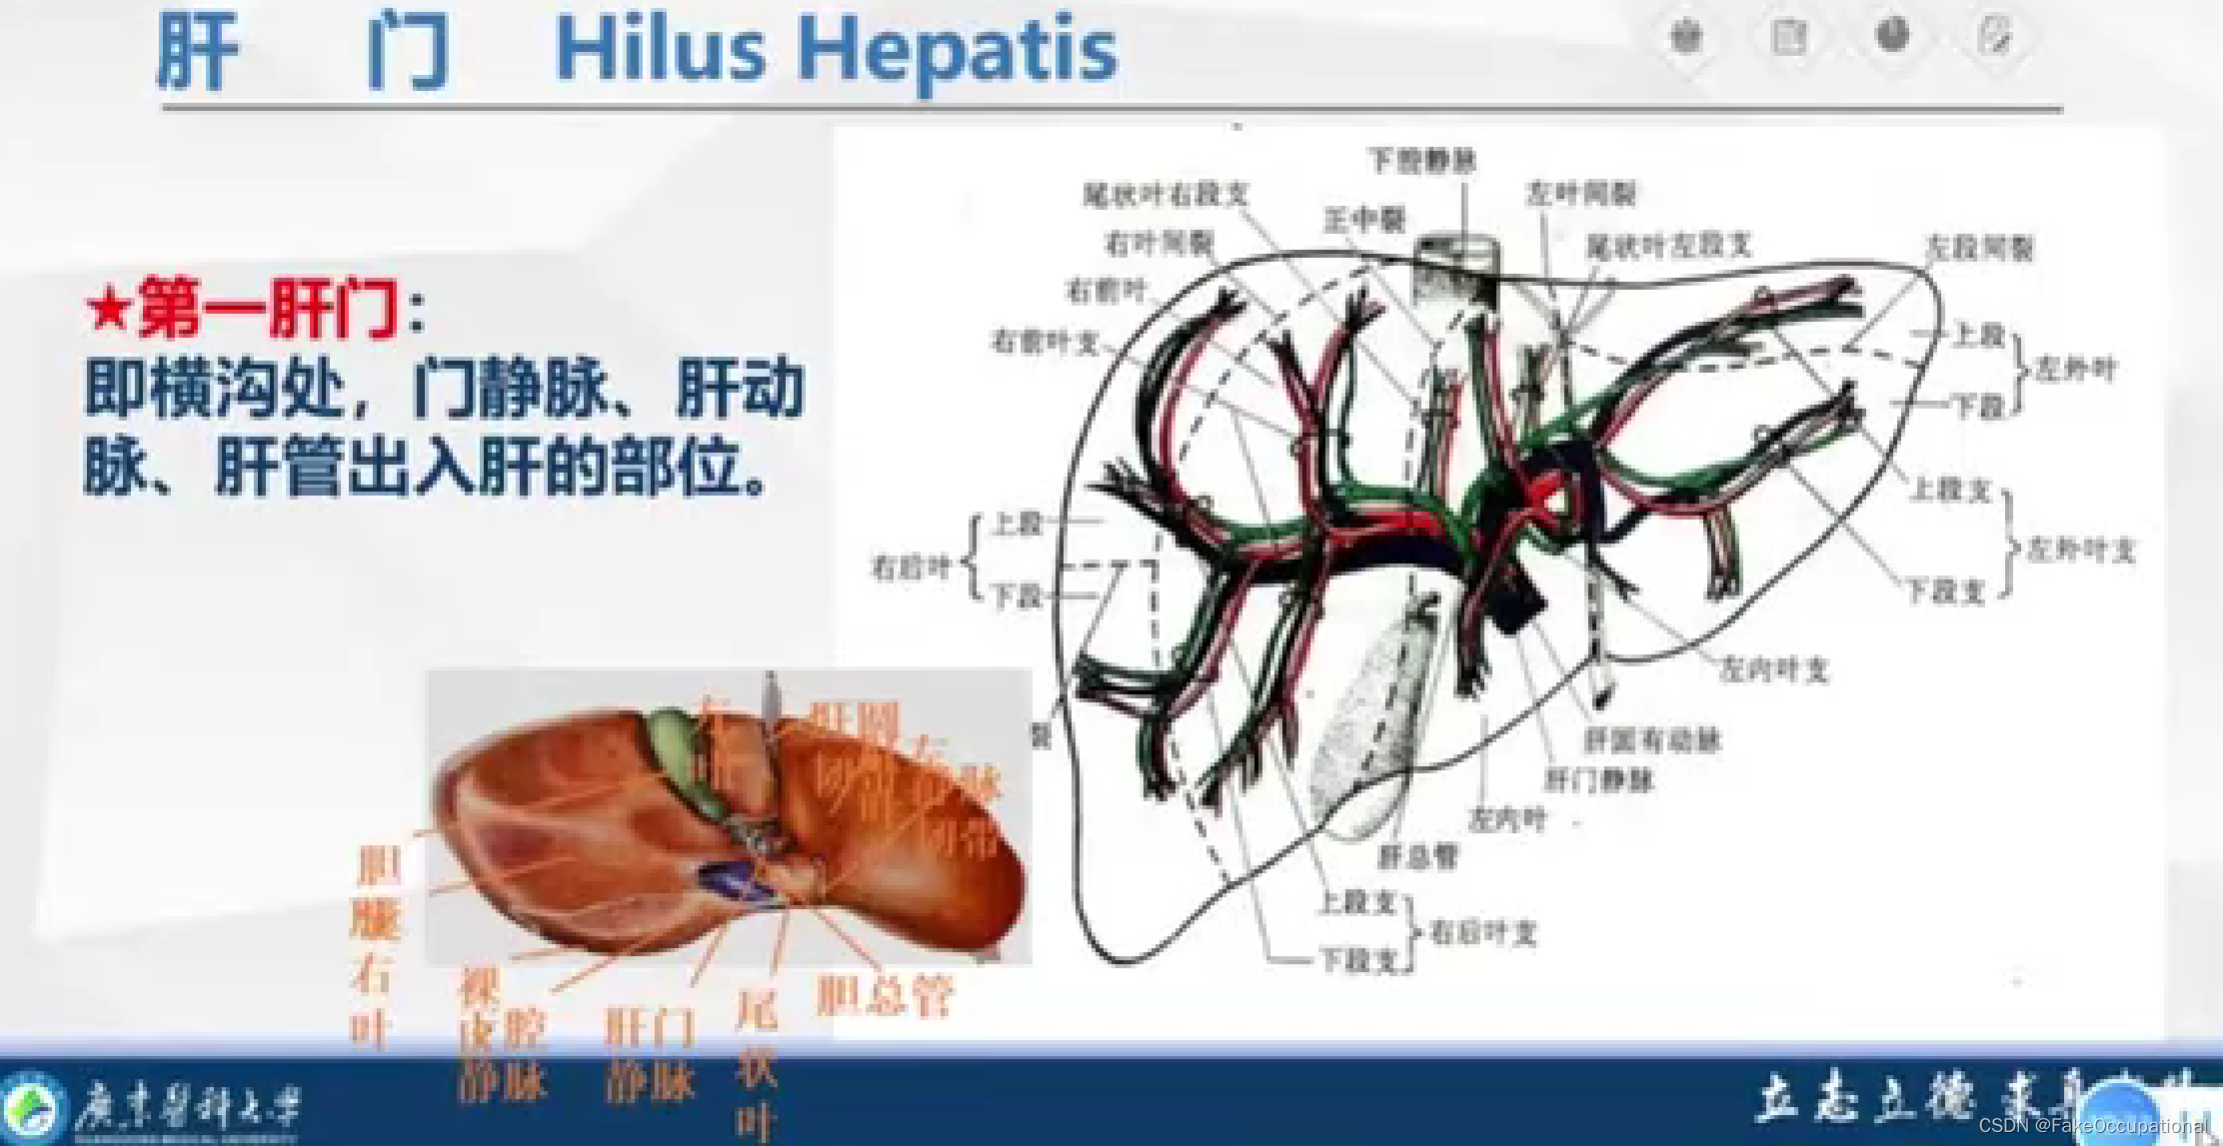

肝脏解剖概要